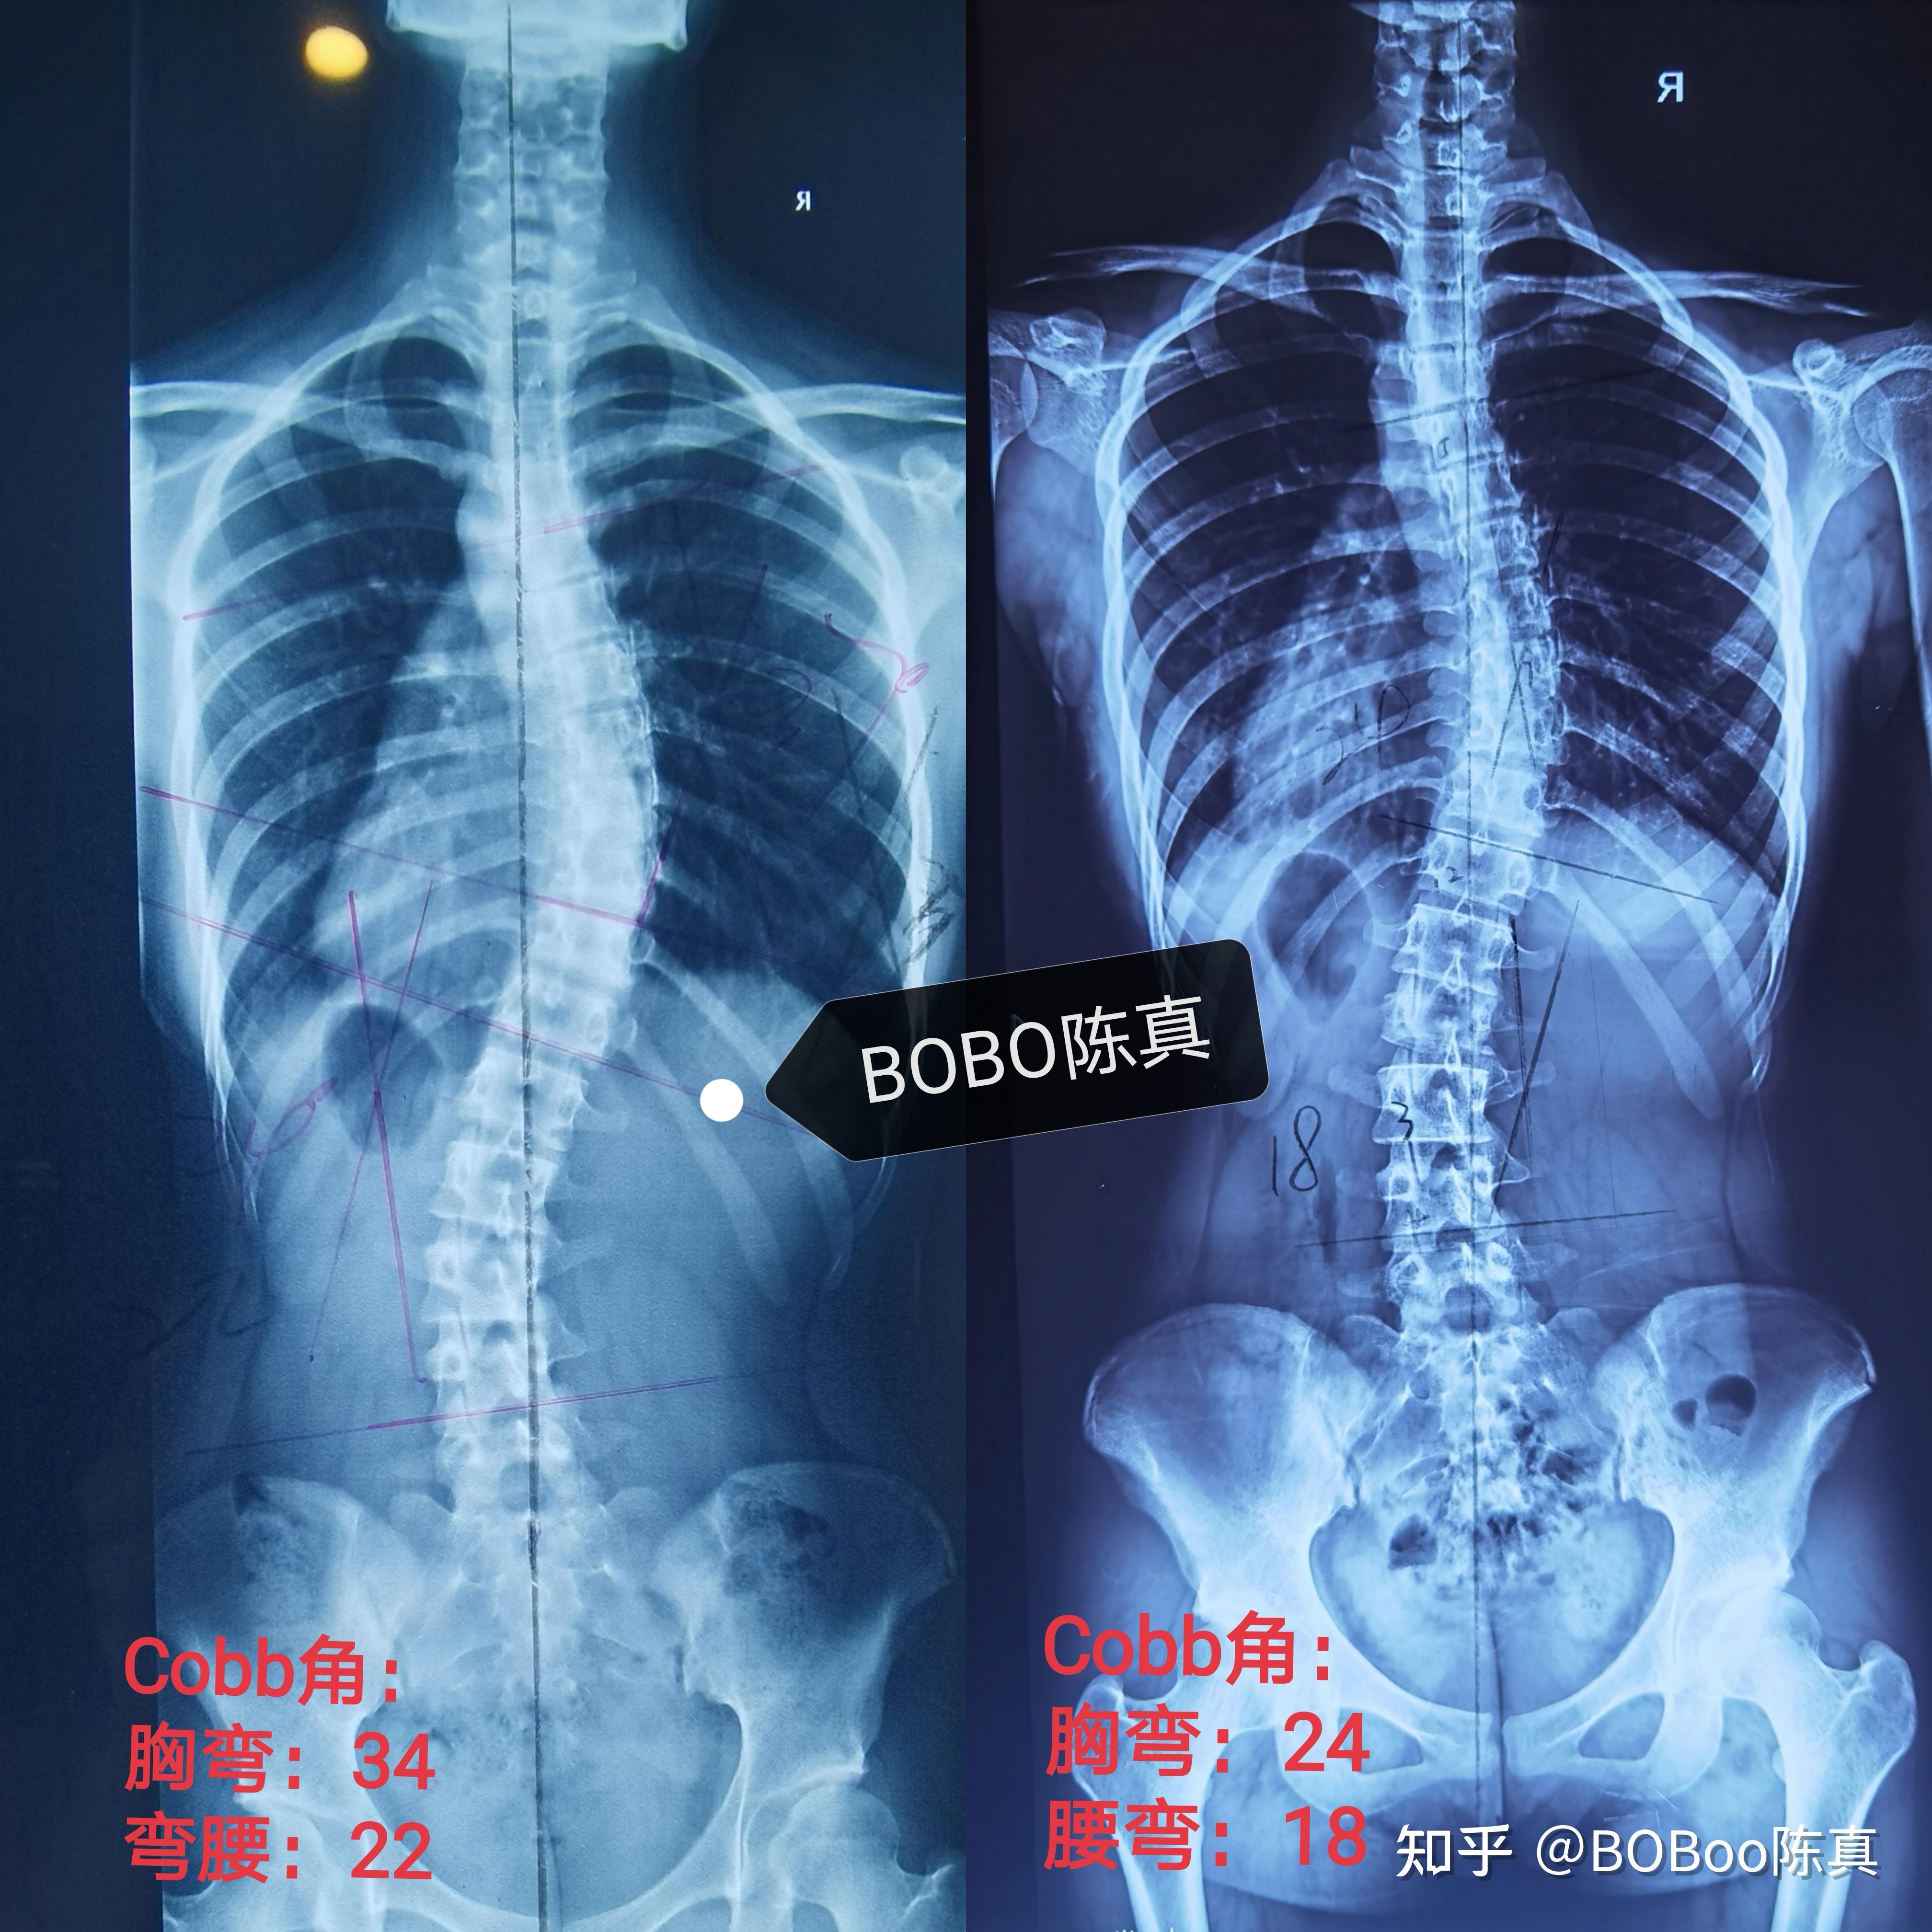

脊柱侧弯40度

脊柱侧弯超过40度,不一定要做手术05 赵同学979911岁那年,是一